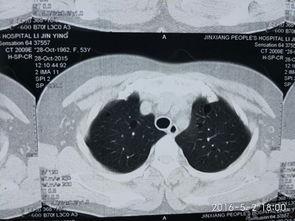

肺上界叩诊的主要目的是检查肺部是否有异常,如肺炎、肺结核等。